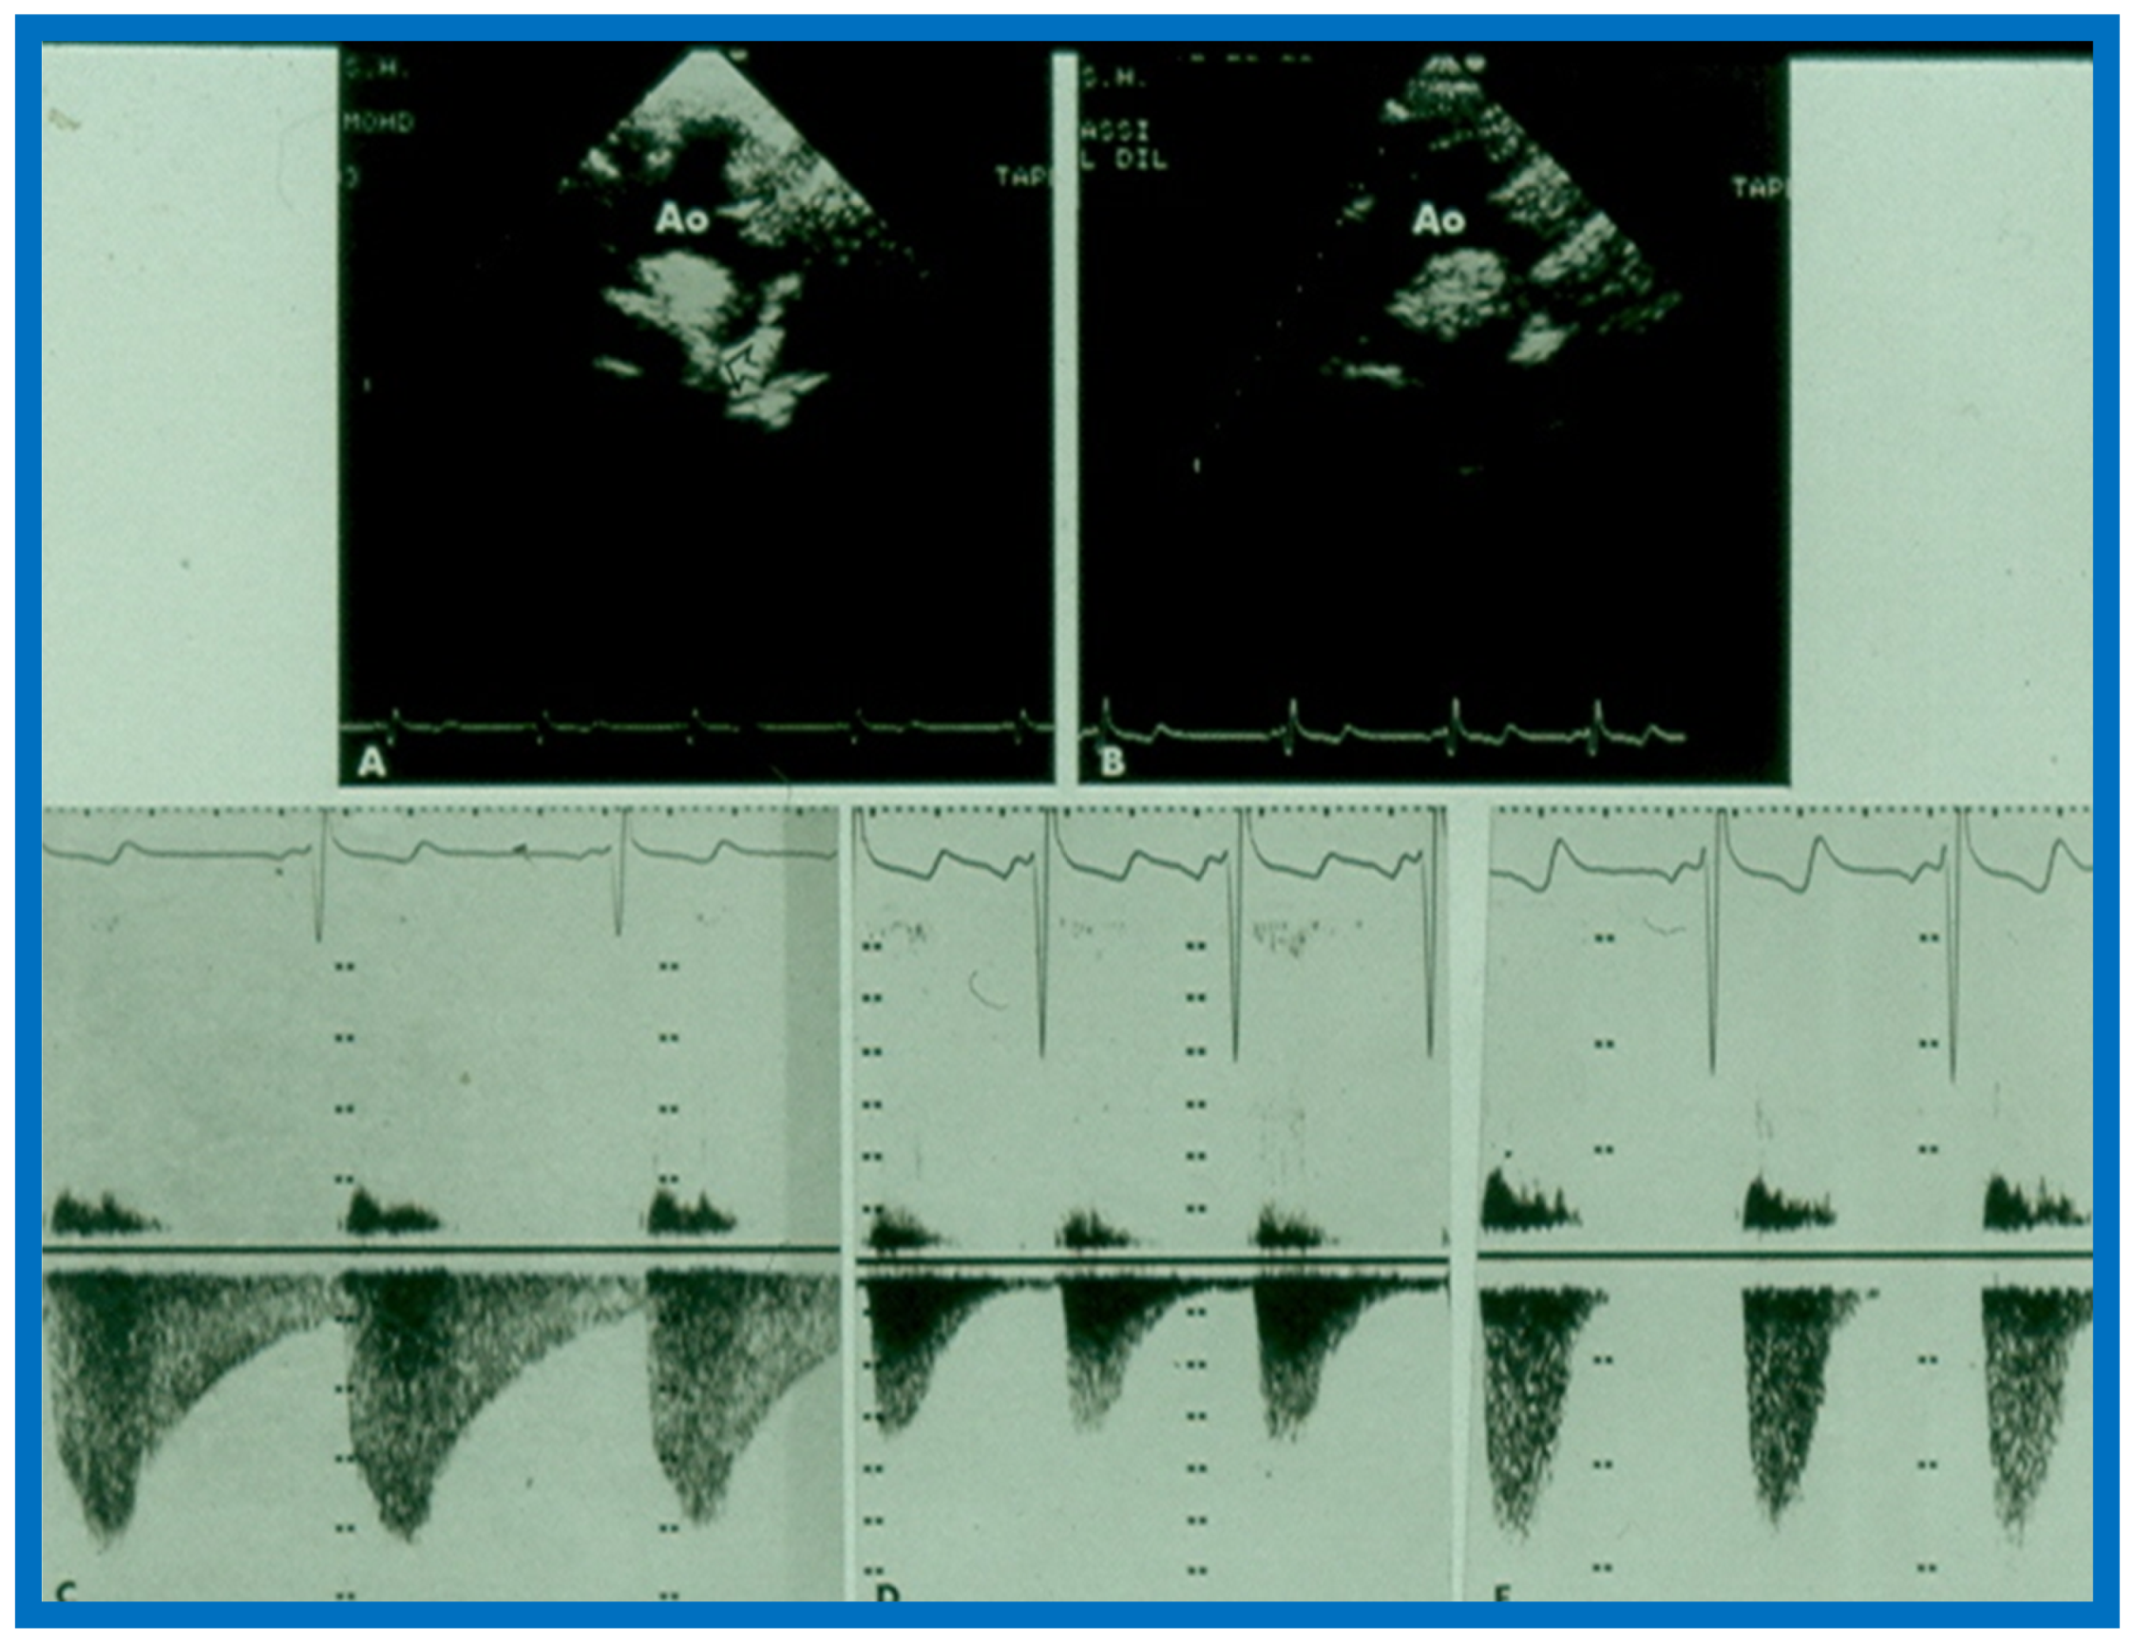

Examples of improvement in LV dimension on echo studies are shown in Figure 40 and Figure 41. The cardiac size and pulmonary venous congestion on chest roentgenograms improved in the hydralazine group (Figure 42 and Figure 43). No significant changes in any of these parameters occurred in the control group.

Figure 40.

Selected M-mode recording from the parasternal short axis view of the left ventricle (LV) prior to (A) and following (B) hydrazine therapy. Note the significant improvement in the LV size and function.

Figure 41.

Selected M-mode recording from the parasternal short axis view of the left ventricle (LV) prior to (A) and following (B) hydrazine therapy from a different infant. Also, note the significant improvement in the LV size and function.